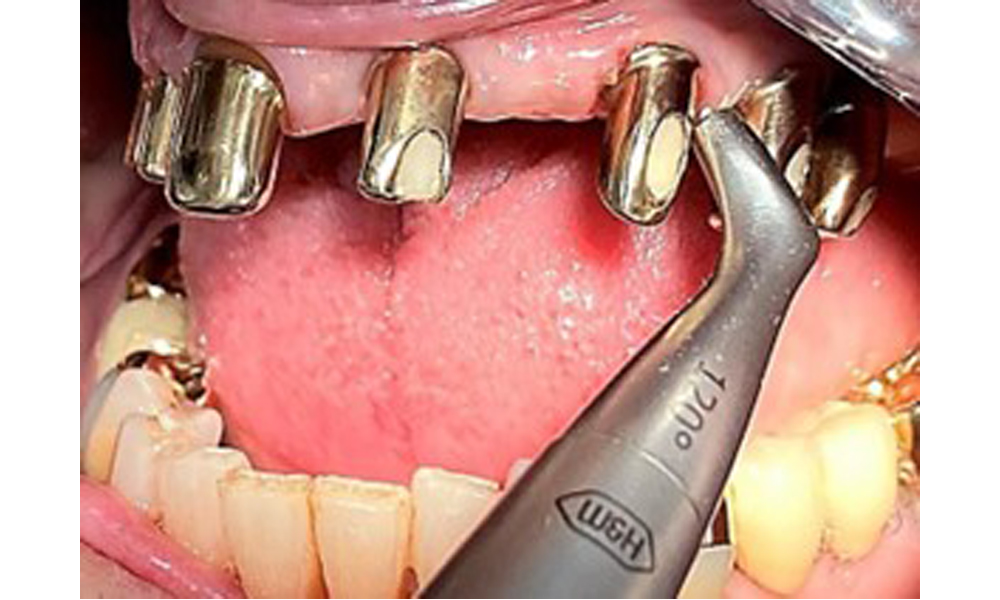

Occlusal view of the mandible.

Fig. 4: Occlusal view of the mandible.

The dental findings are as follows: Combined removable implant and tooth-supported telescopic prostheses on implants 15, 13, 21, 23, 24, 25 and tooth 11 (Fig. 1, Fig. 2, Fig. 3). The patient was fitted with a fixed mandibular denture. Adequate bridges were present over 37 to 34 and 45 to 47 (Fig. 4), the crown margins were intact and there were no active caries. A composite filling with a marginal gap was present on tooth 43. There was mandibular gingival recession, exposing 1 to 3 mm of root surface. This also applies to 11.